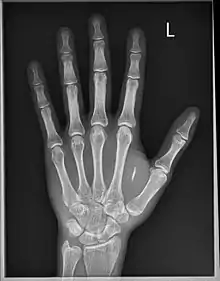

Dangerous Things built the first personal publicly available implantable NFC compliant transponder in 2013.[4] In September 2020, Dangerous Things began another highly successful crowdfunding campaign to realize the world's first titanium encased fully bio-compatible sensing magnet, named the Titan.